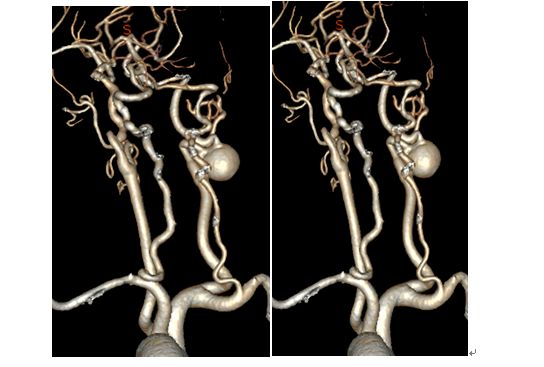

CTA

术前造影显示颈动脉C1-C4闭塞

术后一月复查CTA,见颈动脉闭塞段通畅。